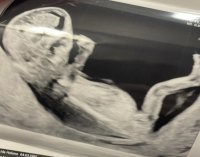

Vårt bilde var 99% jente, når vi sendte det inn. Skikkelig tydelig nub var det også.

Han er kjempe gutt.

Klart det!Interessant. Vil du dele bildet?